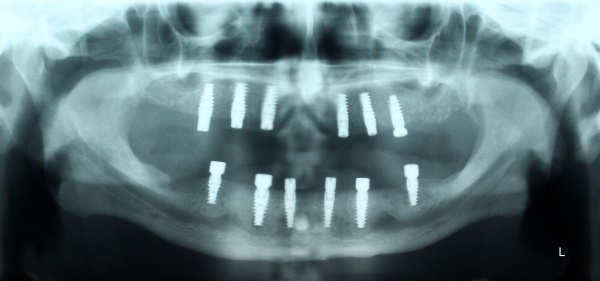

Nach achtwöchiger Ausheilzeit wurde im Mai 2012 eine 3D-Planung der Implantation bei unklarem Knochenangebot durchgeführt. Hierzu erfolgte bei Zahnlosigkeit zur Verankerung der Planungsschablonen im Juni 2012 die Insertion von drei Miniimplantaten im Oberkiefer und drei Miniimplantaten im Unterkiefer. Zur besseren Stabilisierung der schon vorhandenen Totalprothesen wurden Druckknöpfe in die Prothesen eingebracht. Nach Herstellung der Planungsschablonen wurde Ende Juni 2012 eine Denta-CT durchgeführt.

Im Oberkiefer konnten mit der Planungssoftware SkyPlanX der Firma Bredent 6 Implantate mit BoneSplit geplant werden (Abb. 2), im Unterkiefer war eine Implantation aufgrund ungenügenden Knochenangebots nicht möglich.

Im August 2012 erfolgten die 3D-gestützte Implantation (6 Implantate, Firma Nobel Biocare, System Active) im Oberkiefer mit Bone Split sowie eine An- und Auflagerungsosteoplastik vom linken Beckenkamm im Unterkiefer nach Entfernung der Miniimplantate (Abb. 3). Nach komplikationsloser Einheilung wurde im Dezember 2012 die Materialentfernung und Implantation im Unterkiefer (6 Implantate, Firma Nobel Biocare, System Active) durchgeführt (Abb. 4). Die Osseointegration verlief ungestört. Aufgrund der ungenügenden Weichgewebssituation im Unterkiefer erfolgte an jedem Implantat bei Freilegung eine Vestibulumplastik mit Einlagerung einer bioresorbierbaren Membran (Firma Botiss, Mucoderm, Abb. 5 und 6). Die endgültige prothetische Versorgung erfolgte durch den truppenzahnärztlichen Kollegen in der Stammeinheit des Patienten (Zahnarztgruppe Nordholz / SanZ Celle) mit einer gaumenfreien implantatgetragenen Teleskopprothese im Ober- und Unterkiefer, die eine festsitzend-herausnehmbare vollständige stomatognathe Rehabilitation des Patienten ermöglichte (Abb. 7 und 8). Er wurde zum halbjährlichen Recall angehalten.